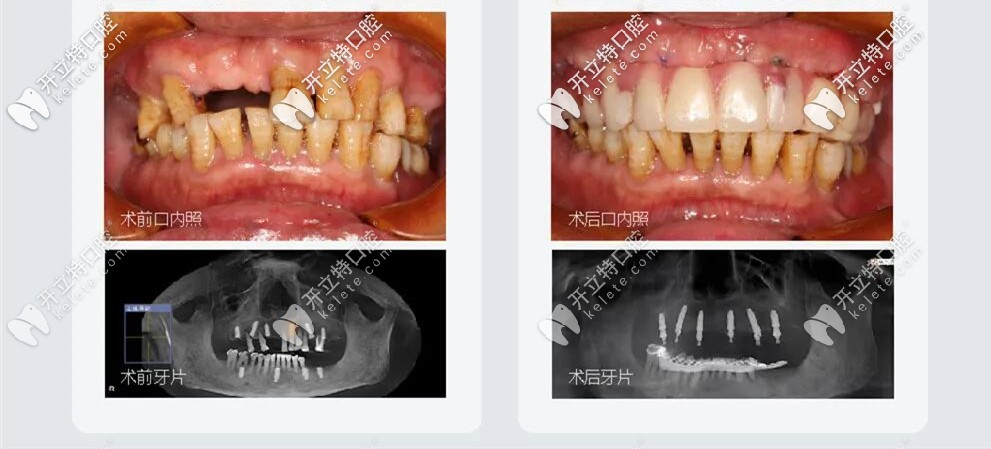

All-on-6種植牙前后照

王叔叔的孩子們?yōu)榱俗约旱睦习帜馨蚕硗砟辏院煤群?,在百般勸說(shuō)下帶著王叔叔來(lái)到了成都極光口腔找劉東偉醫(yī)生做的種植牙;劉醫(yī)生結(jié)合顧客需求以及自己的經(jīng)驗(yàn),采取的方案是:拔除松動(dòng)的牙齒,用極光美式定制植牙All-on-6微創(chuàng)種植牙技術(shù);王叔叔當(dāng)天植牙,當(dāng)天戴牙;

微創(chuàng)種植牙治療前后對(duì)比圖

當(dāng)天做完種植牙,就恢復(fù)咀嚼功能啦,種完就回家了,不腫不痛也很輕松。